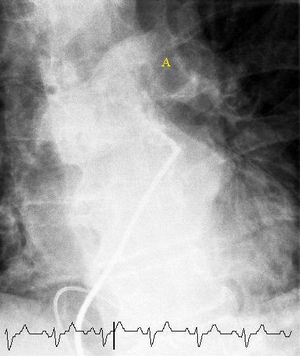

(A) 20 mCi의 제논-133 가스 흡입 후, 후방 투영으로 신티그래피 이미지를 얻었으며, 폐의 균일한 환기를 보여준다.

(B) 4 mCi의 테크네튬-99m 표지 알부민 정맥 주사 후, 신티그래피 이미지가 후방 투영으로 표시된다. 이 외의 다른 영상에서는 여러 영역에서 활동 감소가 나타났다.

환기/관류 스캔(V/Q 스캔, 폐 신티그래피)은 폐의 일부 영역이 혈전으로 막혀 환기는 되지만 혈액 관류가 되지 않는 것을 보여준다.[17] 다중 슬라이스 CT와 정확도는 비슷하지만, CT 기술 발달로 인해 사용 빈도가 줄고 있다. 요오드화 조영제 알레르기, 신장 기능 손상, 임신 등의 경우에 유용하며(CT보다 방사선 노출 적음),[62][63][66] 평면 2차원 영상 또는 단일 광자 방출 컴퓨터 단층 촬영(SPECT)을 이용한 3차원 영상으로 검사할 수 있다.[55] SPECT/CT 하이브리드 장치는 이상 부위의 해부학적 특성 파악에 용이하다.[64]